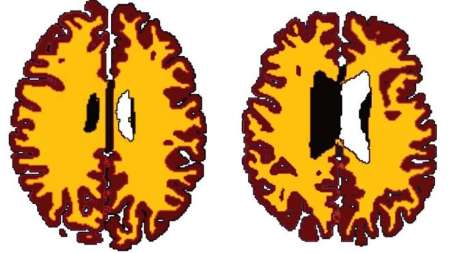

مطالعات محققان دانشگاه کمبریج نشان می دهد اضافه وزن در سرعت کاهش ماده سفید مغز موثر است و مغز یک فرد 50 ساله چاق، 60 ساله است.

چاقی سبب پیری زودرس مغز می شود و مغز افراد چاق نسبت به هم سن و سالان لاغر 10 سال پیرتر است. حجم ماده سفید مغز به طور طبیعی بر اثر افزایش سن کاهش می یابد؛ ولی چاقی این روند را تسریع می کند. ماده سفید مغز مسئول انتقال اطلاعات است.

نتایج نشان می دهد حجم ماده سفید مغز افراد دارای اضافه وزن نسبت به هم سن و سالان لاغرشان کمتر است و این تفاوت از دوران میانسالی به بعد مشهود تر است. محققان احتمال می دهند مغز با افزایش سن آسیب پذیرتر می شود. این مطالعه همچنین نشان می دهد تاثیر اضافه وزن بر بدن بسیار پیچیده و مضرتر از چیزی است که تا کنون تصور می شد.